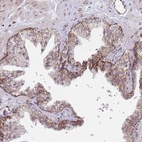

Immunohistochemical staining of human testis shows moderate to strong granular cytoplasmic positivity in Leydig cells.